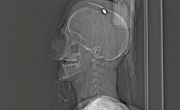

استشهد اليوم الجمعة (24 مارس/آذار 2017) "مصاب الدراز" الشاب مصطفى حمدان (17 عاماً) بعد حوالي شهرين من تواجده في المستشفى، إثر إصابته برصاص حي في الرأس من قبل قوات تابعة للنظام، خلال هجومها على المعتصمين عند منزل آية الله قاسم بالدراز في 26 يناير/كانون الثاني 2017.

ذكرت معلومات أن صحة المصاب مصطفى حمدان (18 عاما) تدهورت بسبب عدم تلقيه الرعاية الطبية الكافية في مستشفى السلمانية، على الرغم من إصابته الحرجة برصاصة في الرأس.

قالت الجمعية البحرينية لحقوق الإنسان إنها تابعت "واقعة قيام عدد من القوات الأمنية الملثمة بمهاجمة المعتصمين حول منزل الشيخ عيسى أحمد قاسم بمنطقة الدراز فجر الخميس (26 يناير/ كانون الثاني 2017) مستخدمة سلاح الشوزن والرصاص الحي مما أسفر عن إصابة الشاب مصطفى حمدان ( 17 سنة ) بإصابة بالغة في الرأس أدت إلى دخوله حالة موت سريري.

والدة مصطفى حمدان: ولدي أصيب برصاصة في رأسه وهو بين الحياة والموت

قالت والدة مصطفى حمدان، الذي أصيب بعد أن فتحت قوات النار على المعتصمين في الدراز، إن ابنها ظل ينزف على الأرض دون علاج، قبل أن يتم نقله لمستشفى السلمانية.